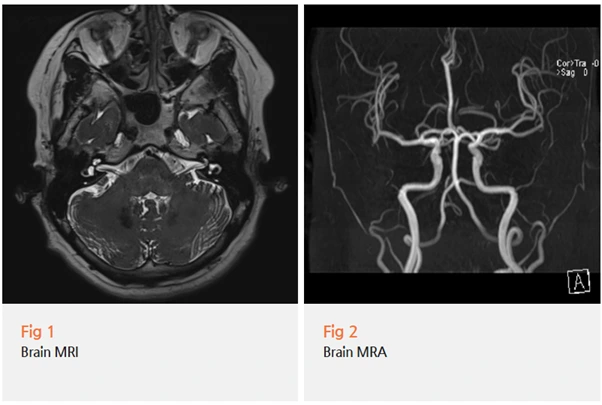

먼저 당일 뇌 MRI와 MRA 검사를 진행했어요.

왜냐하면 삼차신경통을 유발할 수 있는 이차적 원인들을 반드시 배제해야 하거든요.

✔️ 혈관성 병변 (혈관이 신경을 압박하는 경우)

✔️ 뇌종양

✔️ 다발성 경화증

✔️ 뇌간 주변 염증성 질환

이런 질환들도 삼차신경통과 비슷한 증상을 일으킬 수 있기 때문에

꼼꼼하게 확인해야 해요.

검사 결과, 다행히 뇌에 다른 문제는 없었어요.

혈관 압박이나 종양, 염증 소견 모두 관찰되지 않았고요.

그래서 특발성 삼차신경통으로 최종 진단할 수 있었어요.